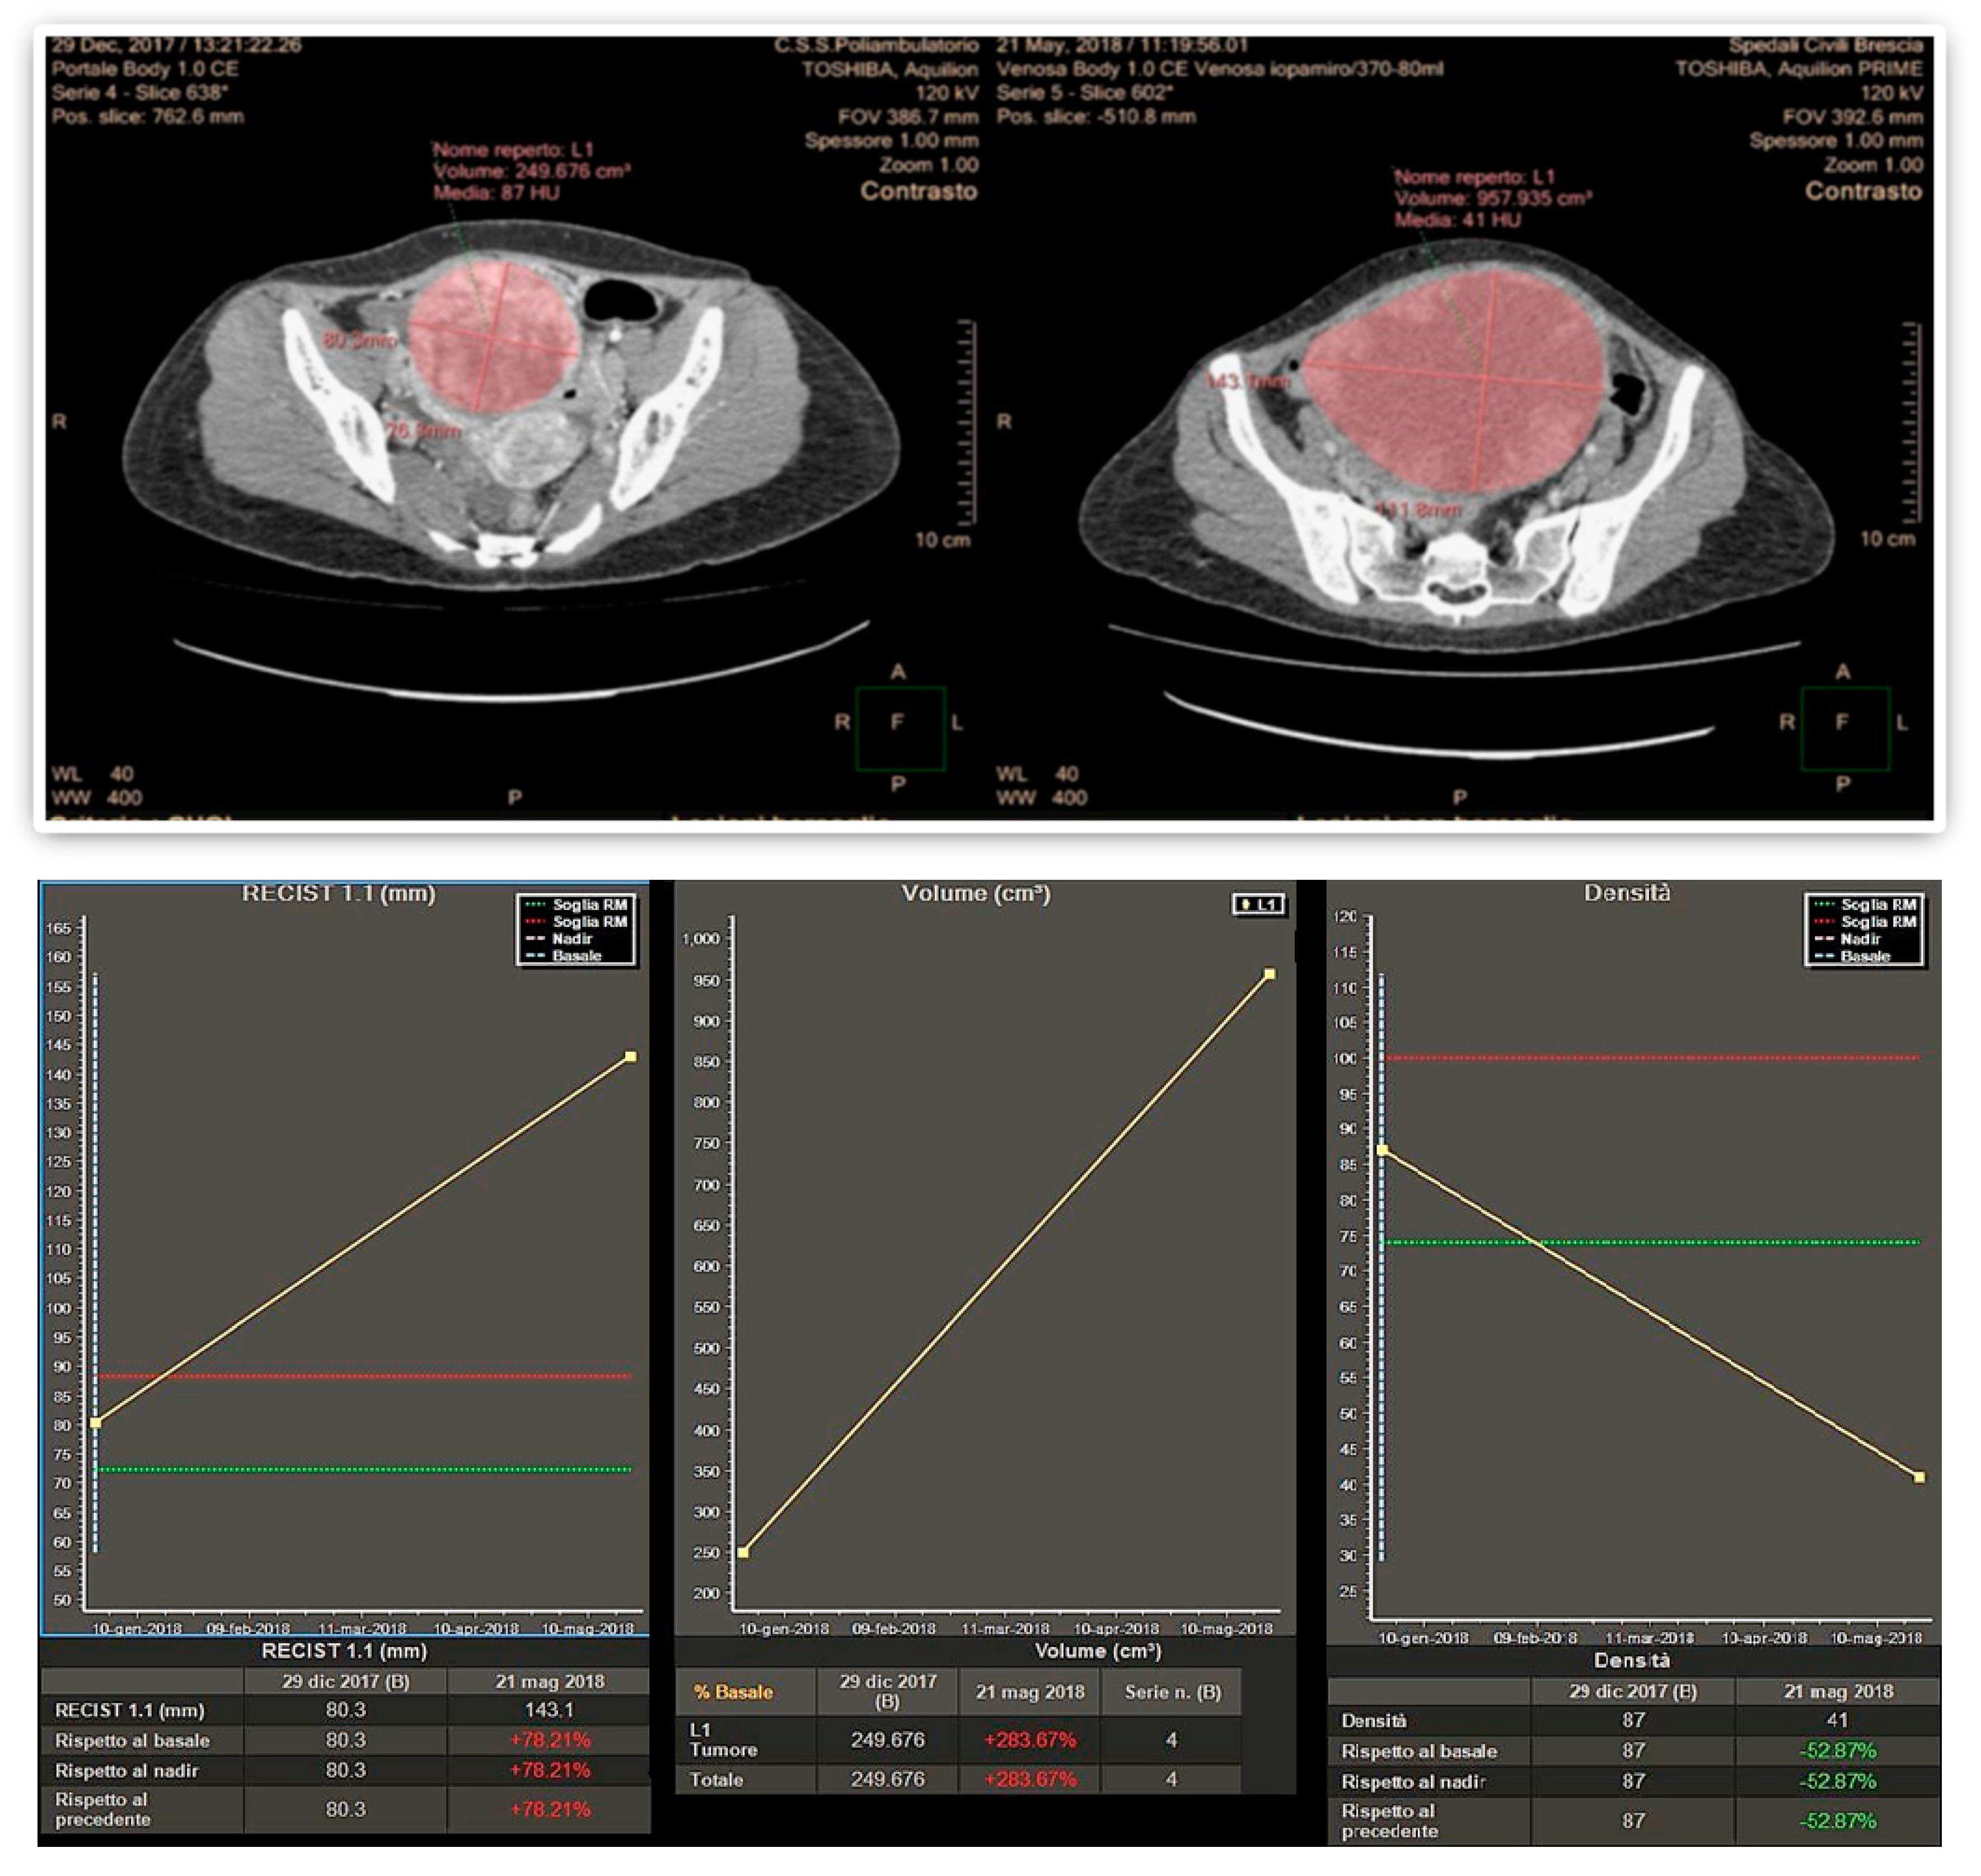

Finally, 10 patients (29.4%) considered responsive by the volumetric criteria were not confirmed by Choi in 1 patient (2.9%) and RECIST 1.1 in another patient (2.9%). An example of a large pelvic secondary implant, considered as a PR using the Choi criteria, otherwise classified as PD when applying RECIST 1.1 and volumetric criteria is shown in Figure 1.

Figure 1. Disagreement in response assessment within the three criteria: according to Choi, the decrease in tumor attenuation was evaluated as a partial response, while according to both Volume and RECIST 1.1 its increase in planar dimensions and volume resulted in Progressive Disease.

Imaging has a pivotal role in objectively defining tumor response or progression of cancer patients during systemic therapy. RECIST criteria, introduced in 2000 [20], are the most standardized, scientifically accepted and currently used system for tumor response evaluation. As mentioned in the introduction, these criteria, even after their revision [14], have several limitations linked to the heterogeneity of the forms and contours of tumor lesions and among different lesions in the same patient. These limitations can be addressed at least in part by the concomitant use of others response criteria. In patients affected by GIST, treated with the tyrosine kinase inhibitor imatinib, Choi criteria demonstrated that the degree of contrast enhancement at CT reflects vascular and interstitial volumes of the tumor, providing information about its structure and biological behavior, even in the absence of size variations [21,22]. In addition, the introduction in clinical radiology of dedicated software allows a fast and semiautomatic segmentation of the analyzed lesions with the automatic measurements of diameters as well as volume and attenuation changes. This approach aims to reduce the subjectivity of the analysis and to detect earlier subtle variations during and after systemic antineoplastic therapy, as well as to shorten the time spent by the radiologist for the manual tumor analysis, while increasing the reproducibility of the evaluation (Figure 1).